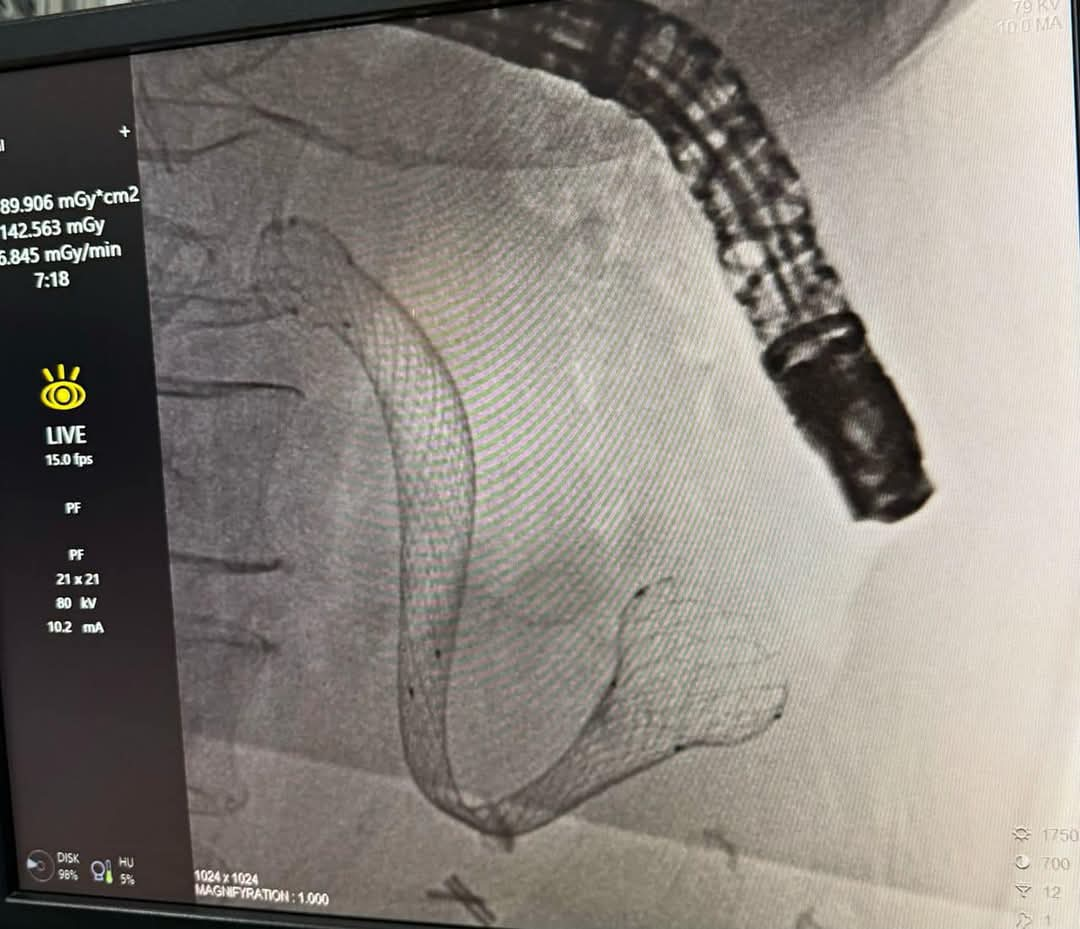

Сарбон Мусоев, заведующий отделением диагностики и лечения Центра, возглавивший операцию, рассказал, что установлен металлический стент типа SEMS (Self‑Expandable Metal Stent) с расширяющимися свойствами. Новая технология позволяет восстановить полноценный пищевой тракт и облегчить состояние пациентов с неоперабельными опухолями желудка и поджелудочной железы, а также при тяжелых доброкачественных стенозах, сопровождающихся язвенными или ишемическими изменениями.

«Операция выполнена под контролем эндоскопии и рентгеноскопии в строгом соответствии с международными стандартами минимально инвазивной хирургии. Благодаря высокоточному оборудованию и использованию современных стентов мы смогли значительно улучшить качество жизни пациента», — отметил С. Мусоев.